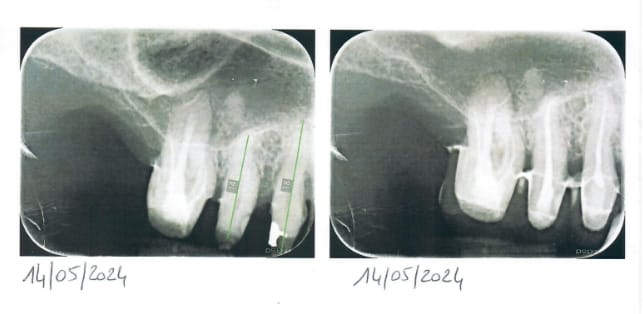

Je me permets de vous soumettre un cas un peu délicat que je suis depuis novembre 2023. Il s'agit d'une patiente pour laquelle nous avions prévu la réalisation de couronnes et bridges sur l'ensemble des secteurs, ainsi qu'un stellite au niveau molaire mandibulaire. Les travaux prothétiques ont été posés le 8 juillet 2024. À ce jour, la patiente présente des douleurs intenses au niveau de la 16, avec une sensibilité marquée à la percussion + une légère mobilité.

Pour 14 15 le test percussion est positif mais bien moins intense que la 16 et aucune mobilité.

Sur le plan historique, j'avais réalisé un traitement endodontique sur 14 et 15, qui s'était avéré particulièrement difficile en raison d'une calcification importante des canaux. Malgré cela, je suis assez satisfait de la qualité des radiographies post-opératoires. En revanche, pour la 16, un retraitement radiculaire n'avait pas été envisagé à l'époque car la dent ne présentait aucun symptôme et le traitement initial, bien que non parfait, ne justifiait pas un retraitement vu le contexte. Je craignais de risquer une perforation sans indication clinique évidente.

Ci joint radio pre et post op du TR de 14 15, je n'ai pas d'autre radio pour le moment mais la radio 16 que j'ai faite cette semaine est la meme que celle jointe

Avec la radio fournie on peut voir une image apicale... Déjà ça sent pas bon.

La 2D est naze comme ça a déjà été dit, mais clairement l'obturation de la racine palatine ne semble pas aller au bout (et oui on voit aussi un élargissement du ligament autour). Cela dit on ne distingue pas non plus de canal dans les derniers mm. Et les vestibulaires on n'y voit rien.